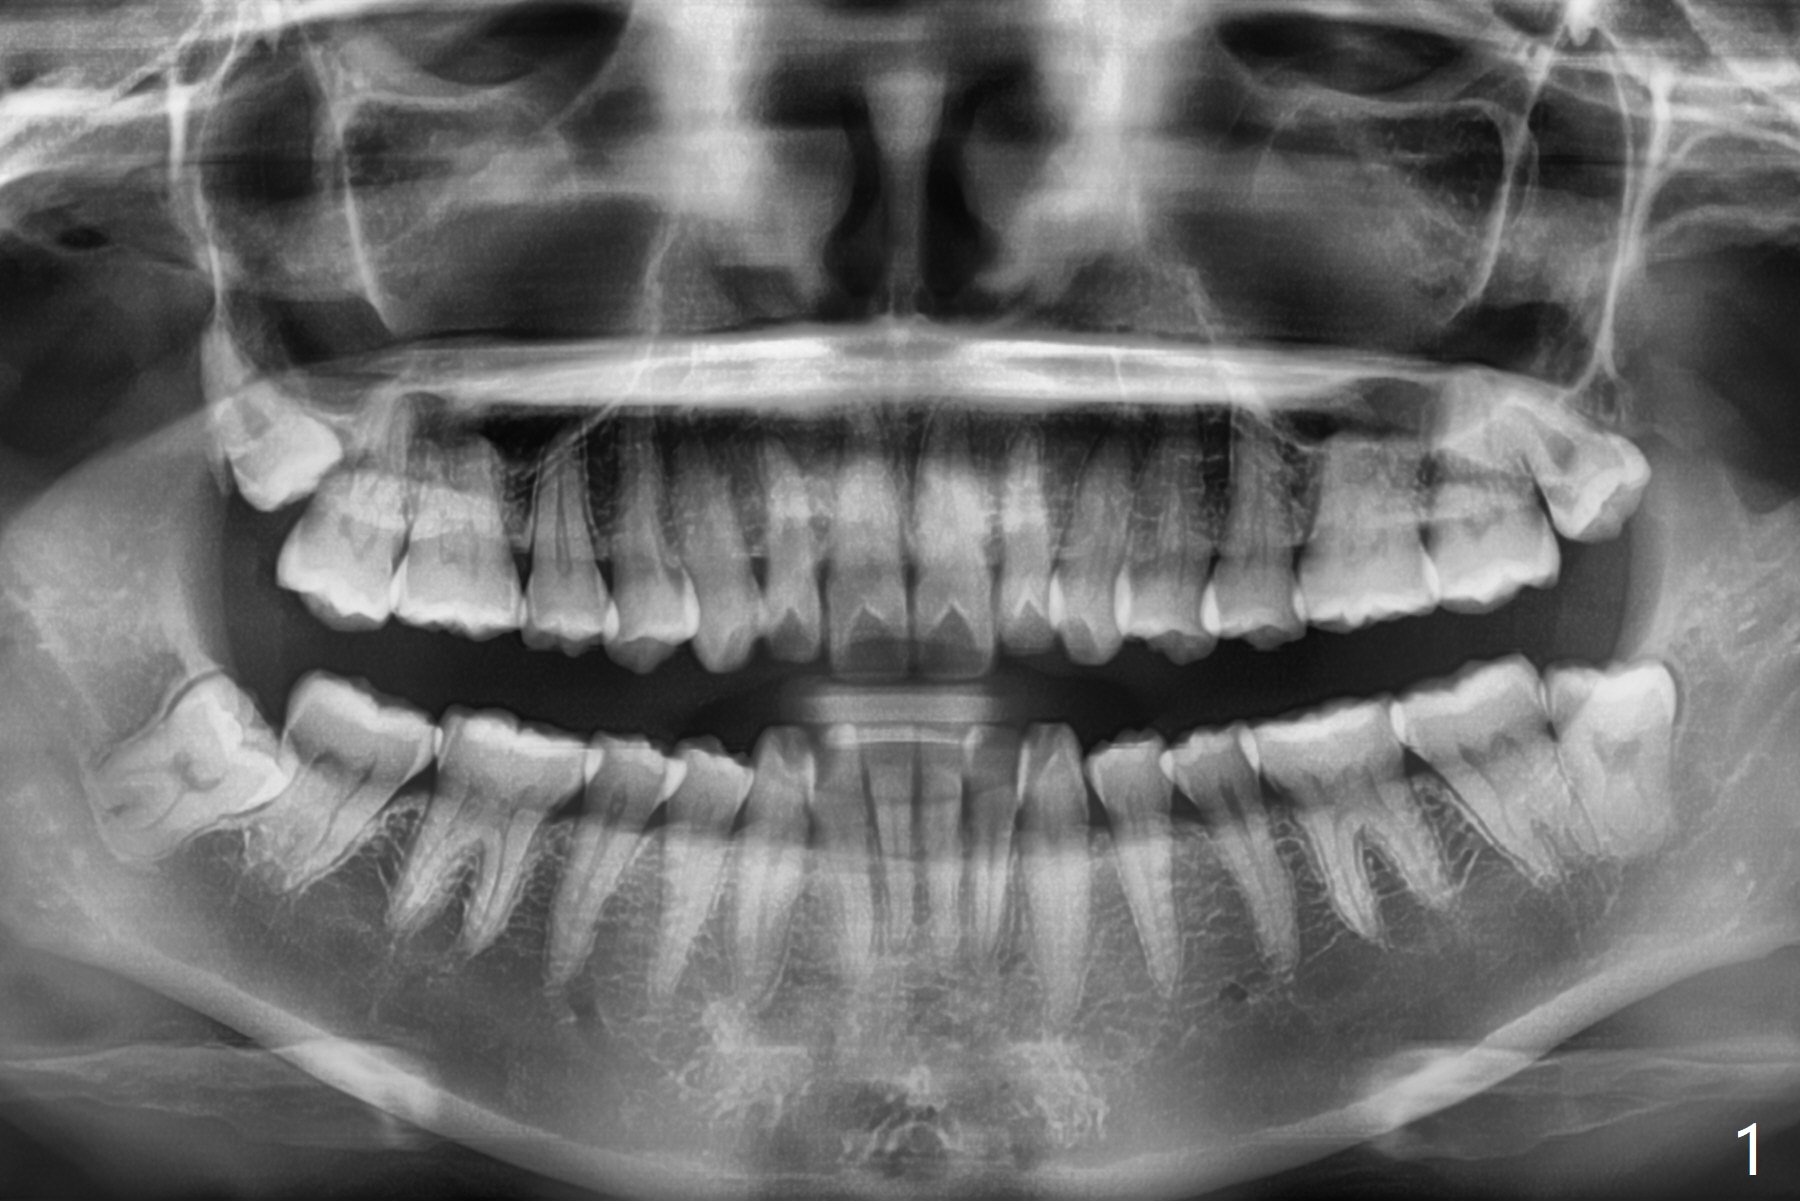

29岁(越过最佳骨再生年龄)女要求拔除左下8,它与7之间骨质非常薄(图一),拔除后需要比较好,便利的植骨材料:医用石膏(Bond Apatite,图二),表面放置1/2胶原塞,4-0 PGA缝合。术后两个月回来拔除左上8(“刺激颊粘膜”,其实远中牙龈红肿),临床上左下8近中颊侧仍有一个小开口,石膏与骨质界限开始不清楚了(图三)。